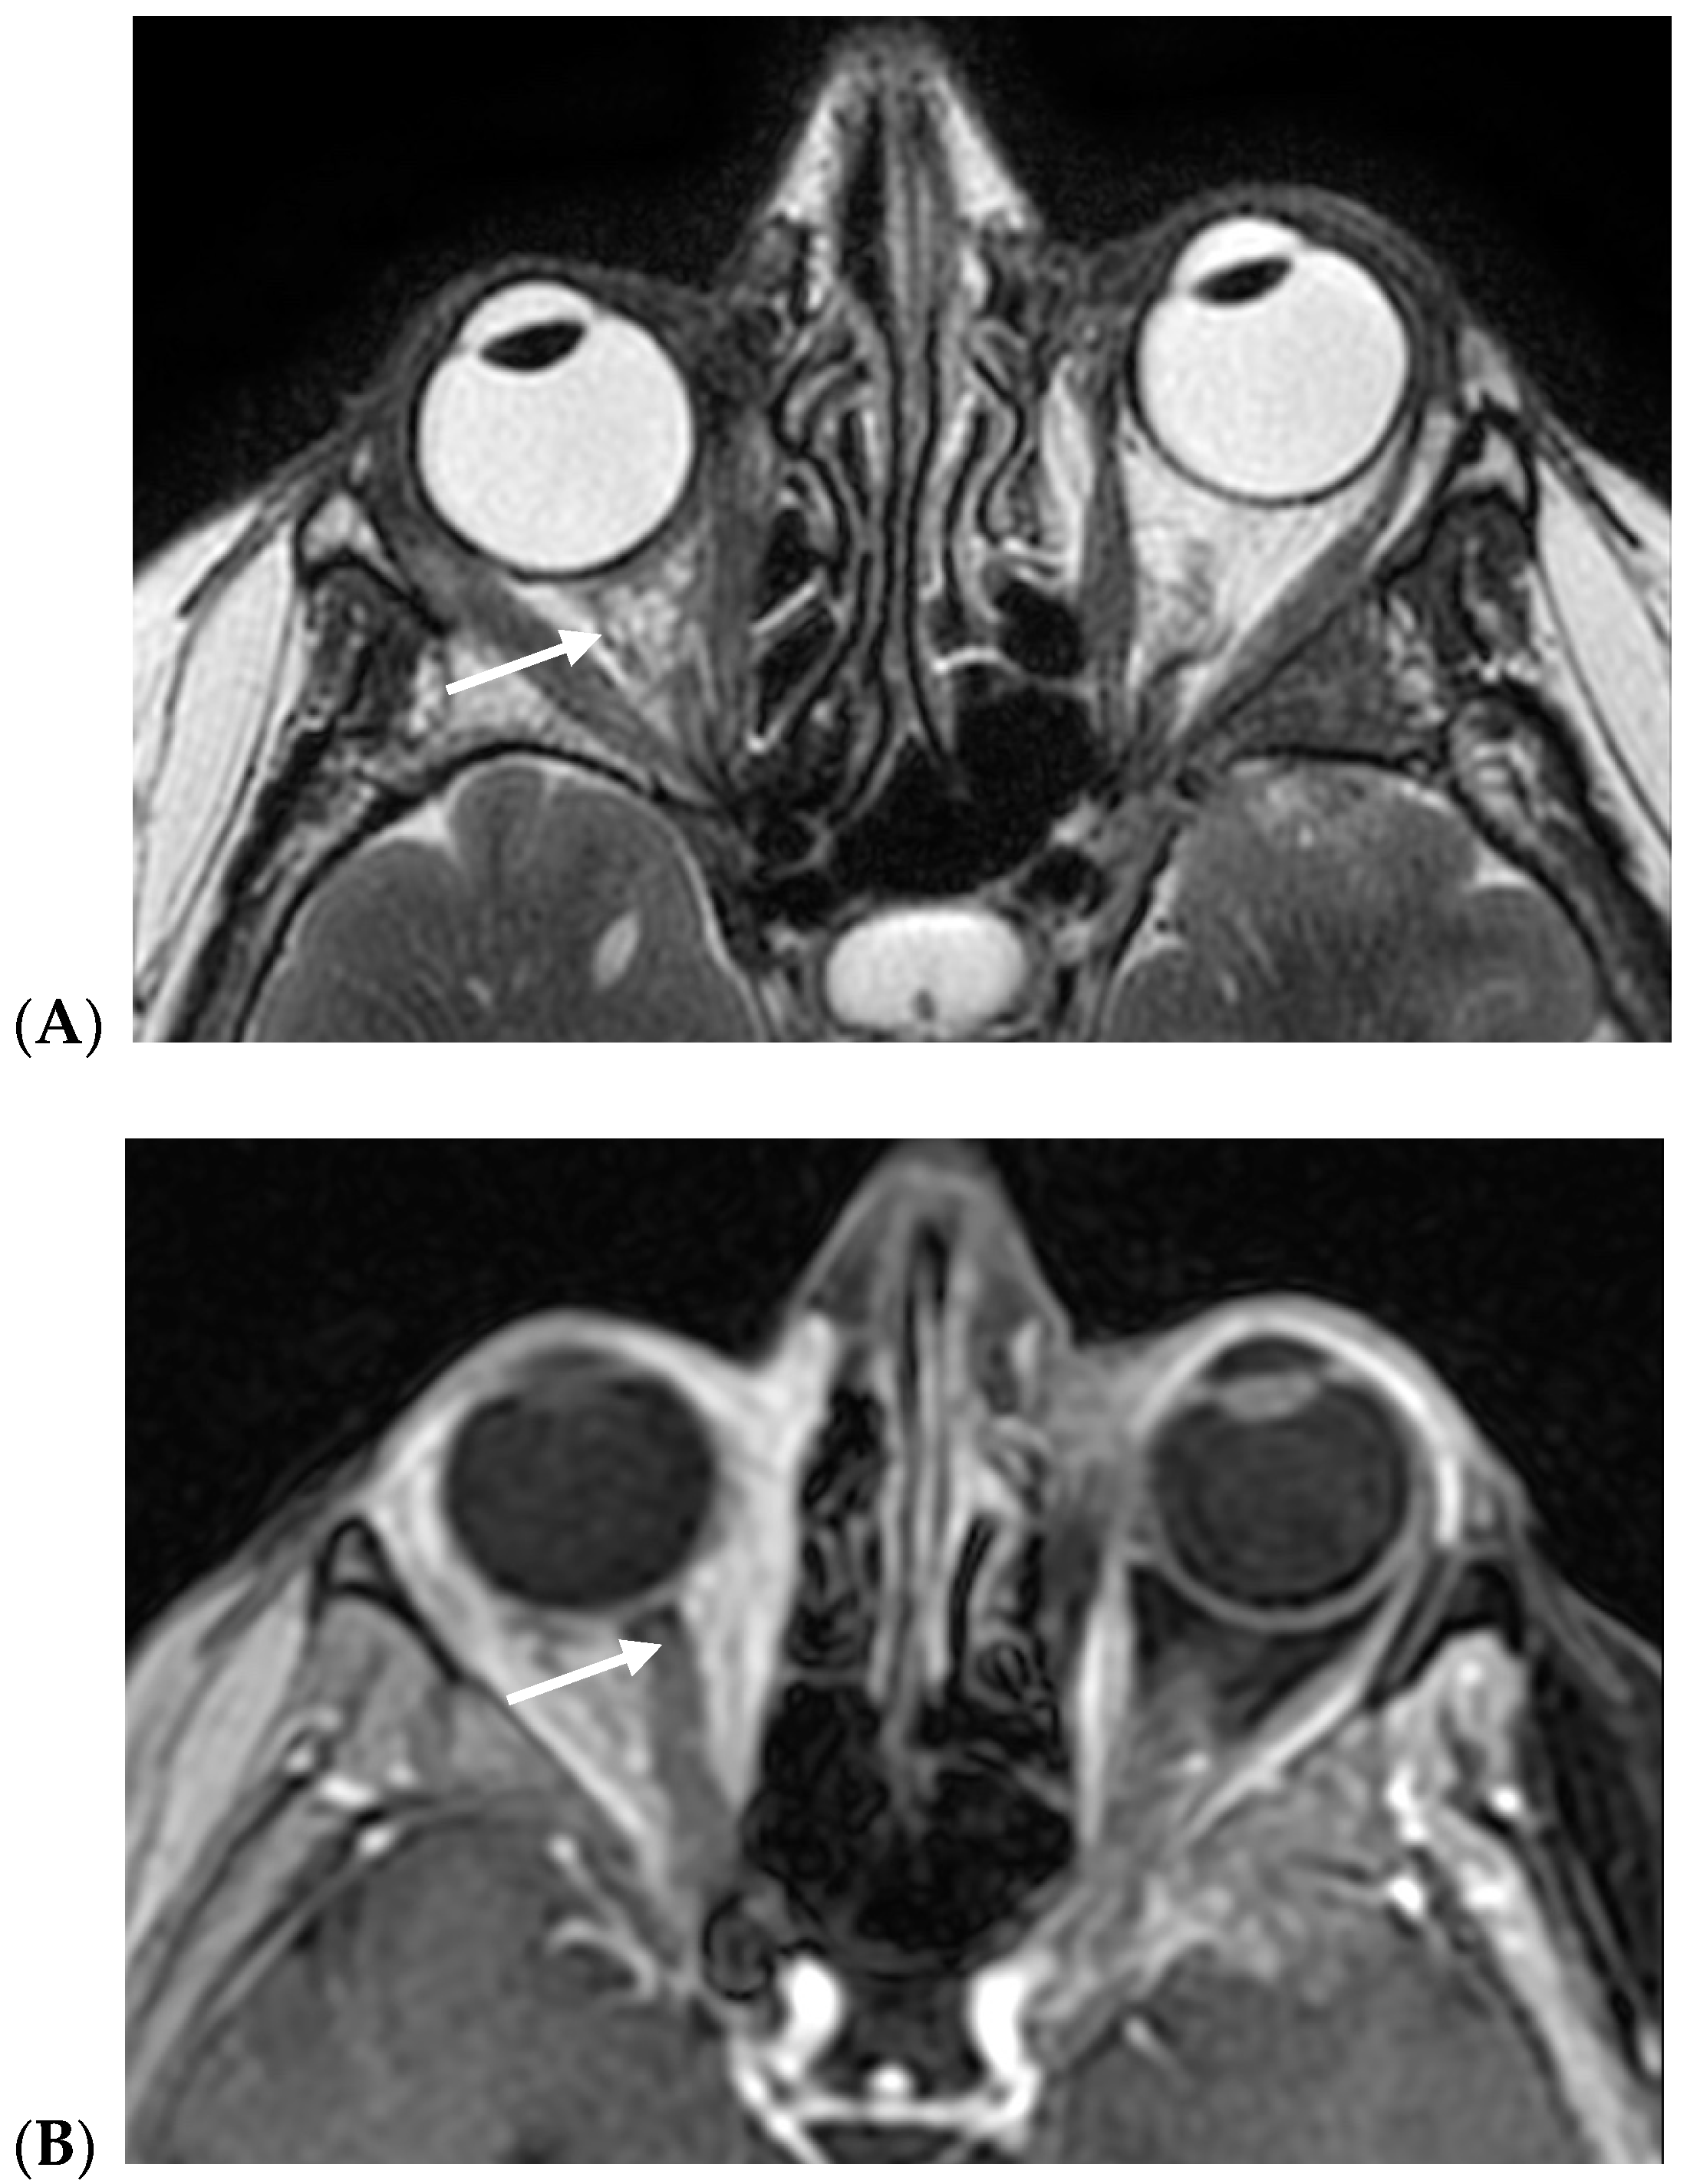

- Russo, C.; Strianese, D.; Perrotta, M.; Iuliano, A.; Bernardo, R.; Romeo, V.; Ugga, L.; Brunetti, L.; Tranfa, F.; Elefante, A. Multi-parametric magnetic resonance imaging characterization of orbital lesions: A triple blind study. Semin. Ophthalmol. 2020, 35, 95–102. [Google Scholar] [CrossRef]